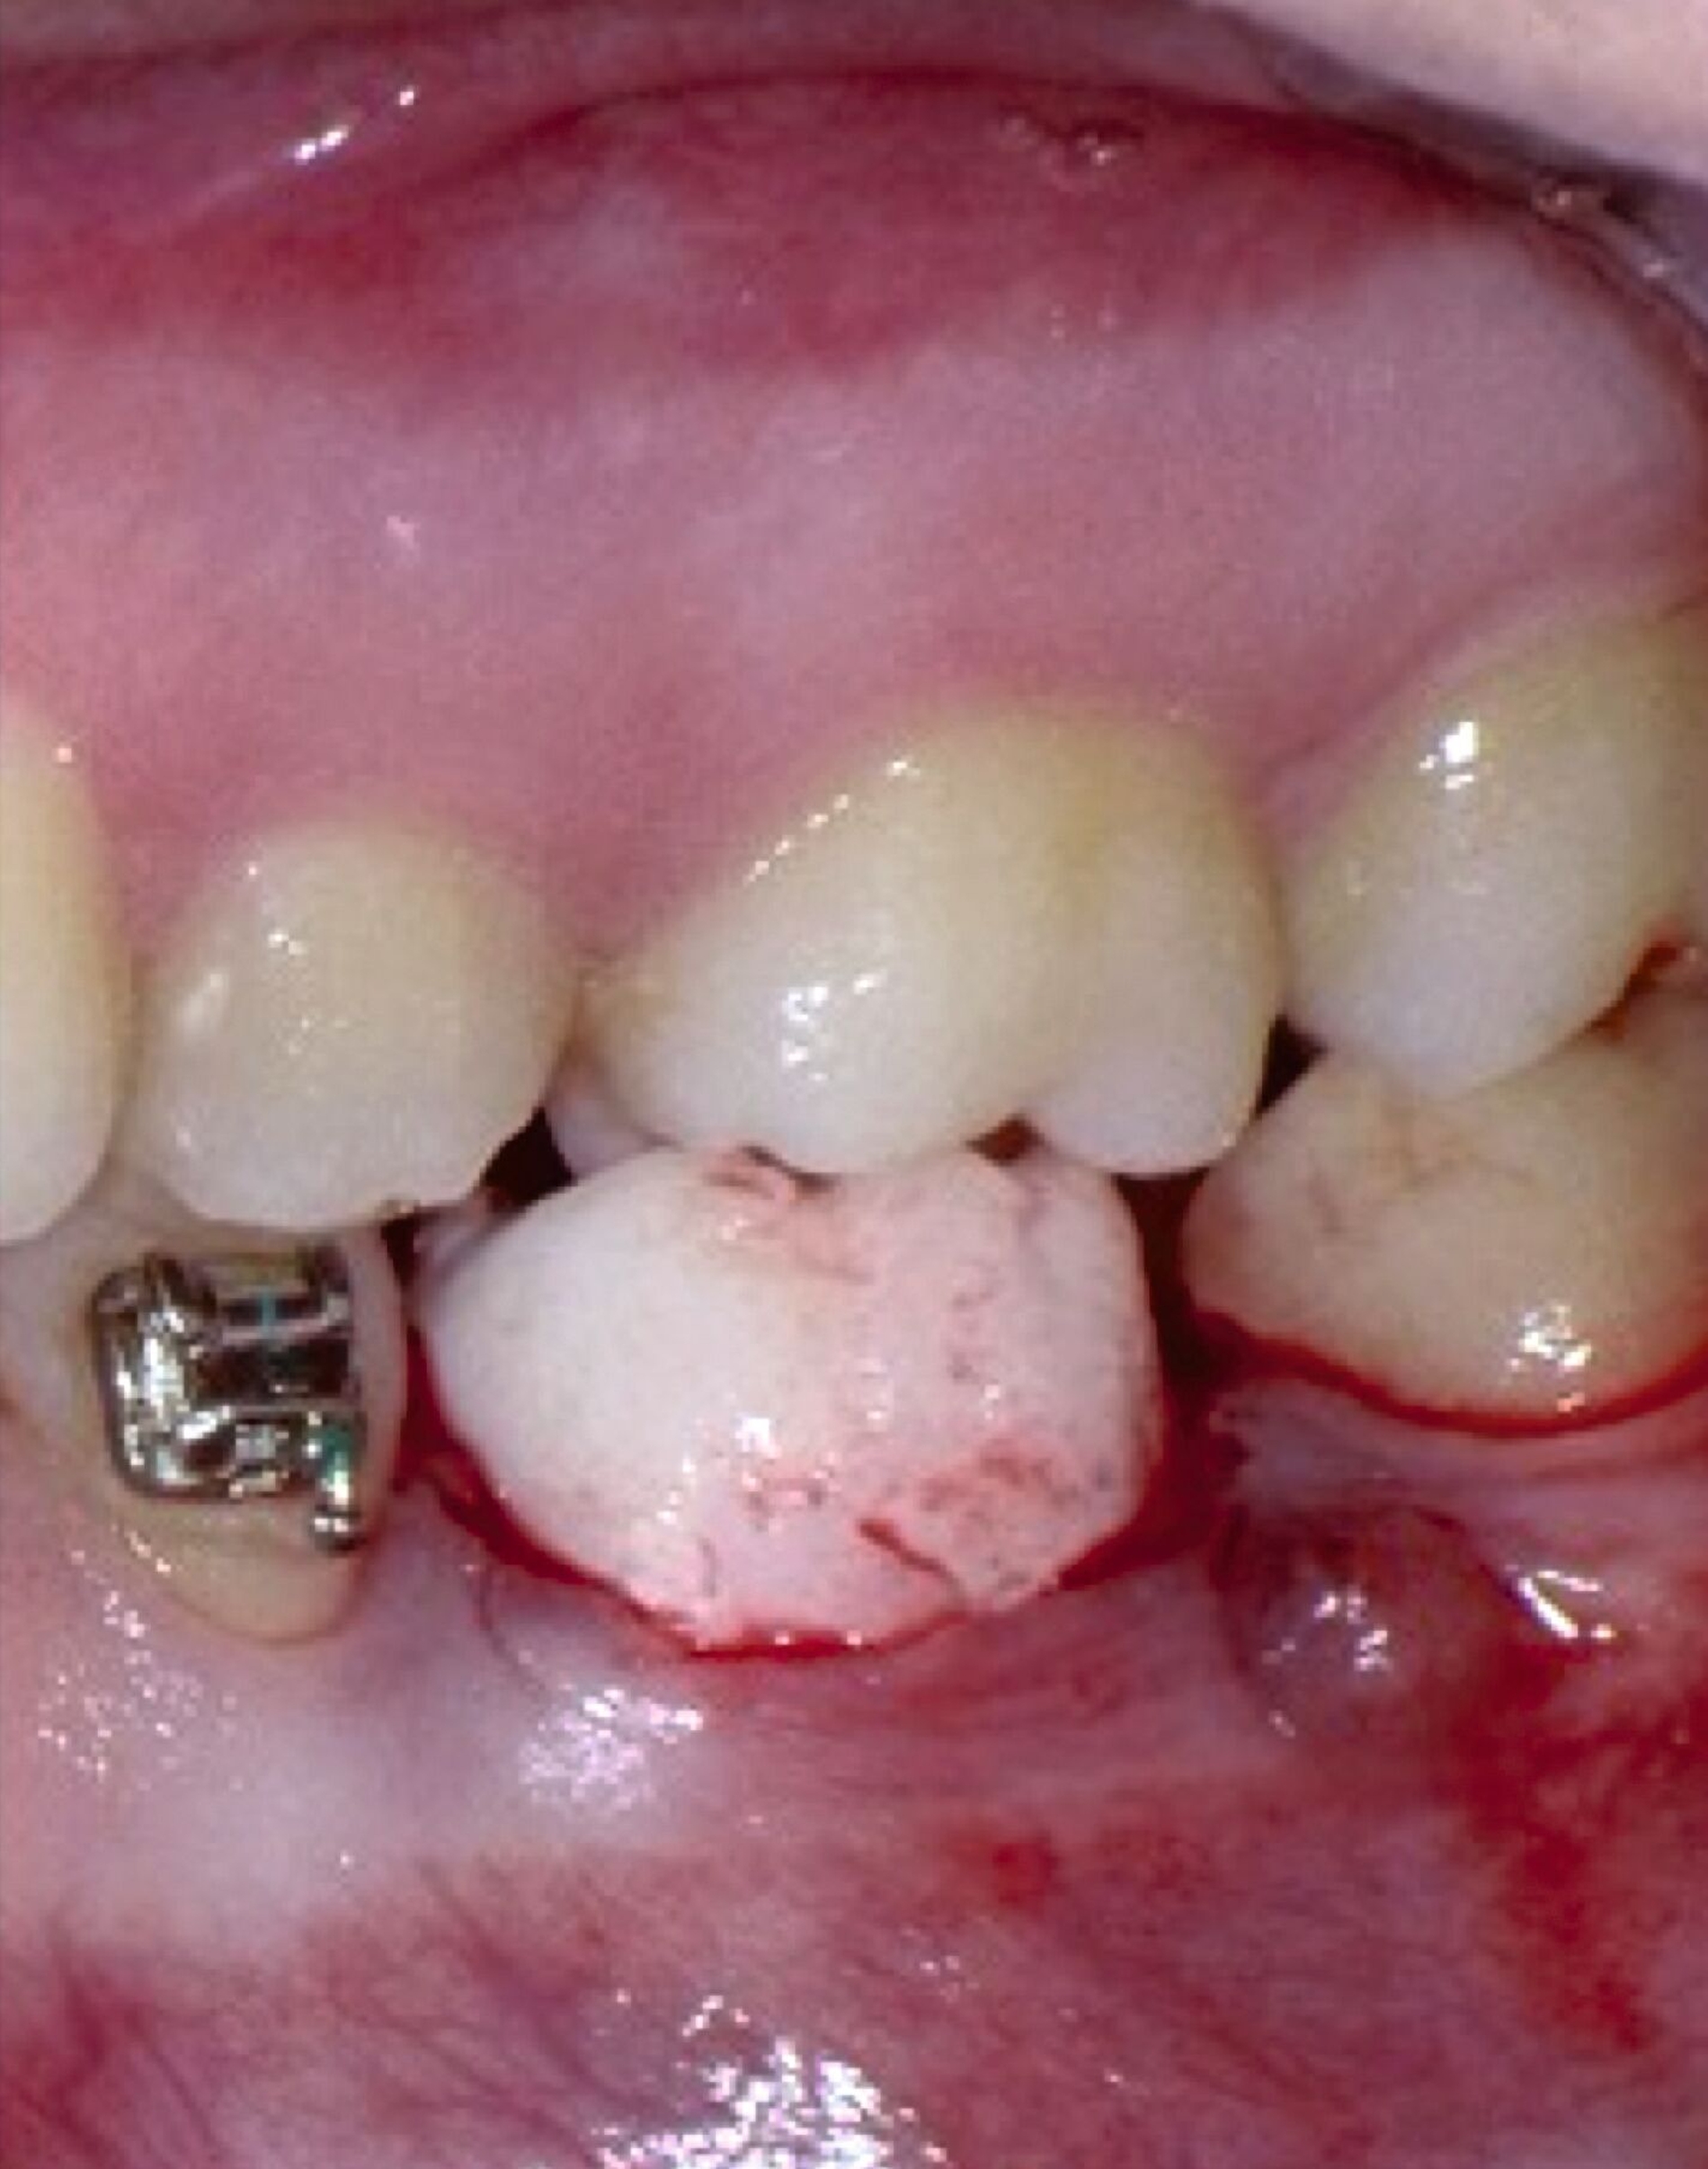

In Absprache mit dem/der zahnärztlich beziehungsweise chirurgisch tätigen Kollegen/in kann die Kieferorthopädie durch Umsetzung verschiedenster 3-D-gedruckter Elemente eine Hilfe in interdisziplinären Behandlungen bieten. Am Beispiel der Zahntransplantation ermöglicht der 3-D-Druck zuvor im DVT segmentierter Zähne eine passgenaue Vorbereitung des Transplantationsbettes (Abbildung 6a). 3-D-gedruckte Zähne können darüber hinaus als Lückenhalter während der kieferorthopädischen Behandlung dienen (Abbildung 6b), bevor eine definitive Versorgung durch den/die zahnärztliche/n Kollegen/in erfolgt.

Weitere Beispiele beinhalten hochkomplexe Behandlungsfälle multipler Zahnanlagen. Während die Extraktionsentscheidung und Absprache mit dem/der chirurgisch tätigen Kollegen/in allein auf Basis der Bildgebung oft limitiert ist, erleichtern 3-D-gedruckte Modelle des segmentierten DVTs sowohl die Entscheidung als auch die Absprache und ermöglichen darüber hinaus eine genauere Planung des chirurgischen Vorgehens (Abbildung 6c). Gleiches betrifft parodontalchirurgische Eingriffe, in denen sogenannte „Cutting guides“ eine zuvor digital geplante Gingivektomie ermöglichen (Abbildung 6d). Im Bereich der Freilegung verlagerter Zähne können Schablonen dem/die chirurgisch tätigen Kollegen/in sowohl die Freilegung des Zahnes (Abbildung 6e) als auch die Anbringung eines Attachments (Abbildung 6f) erleichtern und dabei die kieferorthopädisch gewünschte Attachmentposition passgenau übertragen.